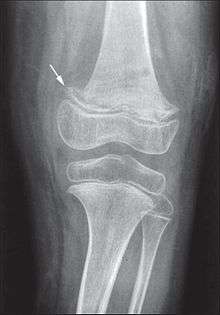

Scurvy is due to not enough vitamin C in the diet.[1] It typically takes at least a month of little to no vitamin C before symptoms occur.[1][2] It occurs more commonly in people with mental disorders, unusual eating habits, alcoholism, and old people who live alone. Other risk factors include intestinal malabsorption and dialysis. Humans and certain other animals require vitamin C in their diets to make the building blocks for collagen. Diagnosis is typically based on physical signs, X-rays, and improvement after treatment.[2]